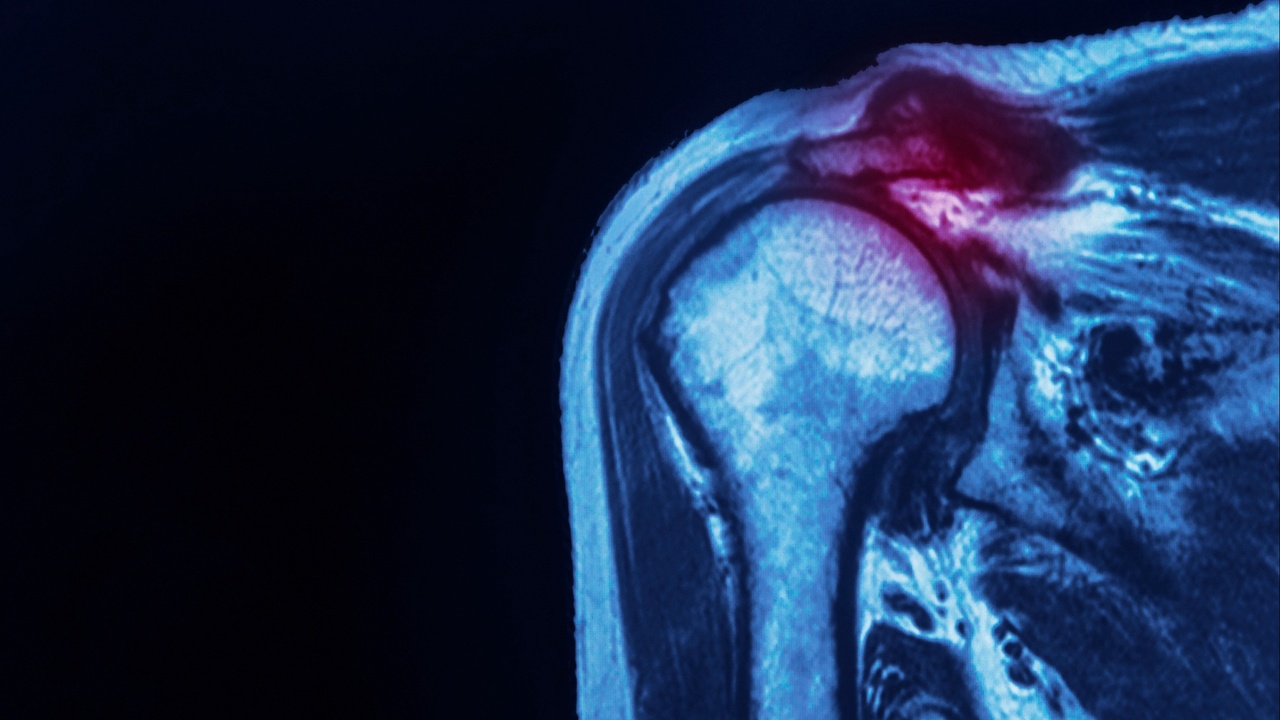

- Causes of ACJ pain including instability/osteolysis/OA